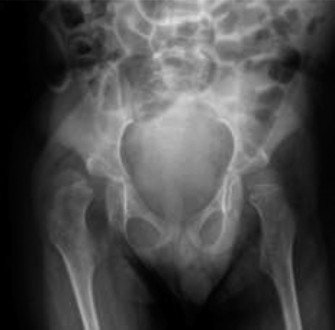

Standard trauma radiographic series, including antero-posterior and lateral projections of the right femur, were obtained upon initial presentation.

The radiographs revealed an acute, comminuted, spiral mid-diaphyseal fracture of the right femur. The fracture pattern demonstrated significant displacement, characterized by overriding of the fracture fragments leading to clinical foreshortening. There was approximately 40 degrees of varus angulation and 30 degrees of external rotation of the distal fragment relative to the proximal fragment.

A critical finding on the plain radiographs was the profound alteration in bone architecture. The diaphyseal cortices appeared markedly thinned, with an abnormally high medullary canal-to-cortical diameter ratio (decreased Cortical Thickness Index). The overall radiolucency of the bone was significantly increased, consistent with severe, generalized osteopenia. The trabecular pattern in the metaphyses was sparse. Importantly, despite the severe osteopenia, there was no radiographic evidence of pre-existing focal lytic or blastic lesions, periosteal reaction, or morphological abnormalities that would suggest an underlying primary bone tumor or metastatic disease.